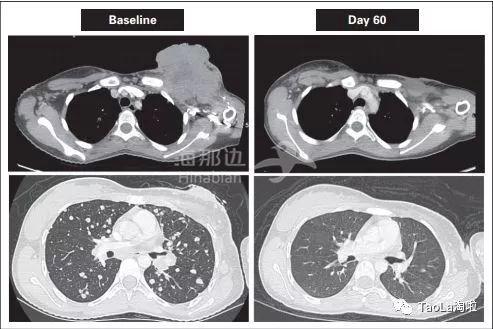

患有乳腺癌的50岁女性治疗前接受过多次的化疗和手术治疗,无奈收关肿瘤还是复发了,情况很严重。在使用了抗癌药Vitrakvi治疗20天之后,裸露的肿瘤几乎消失了。